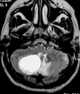

T1-hyperintense extracranial mass

Lipoma

Subacute cephalohematoma